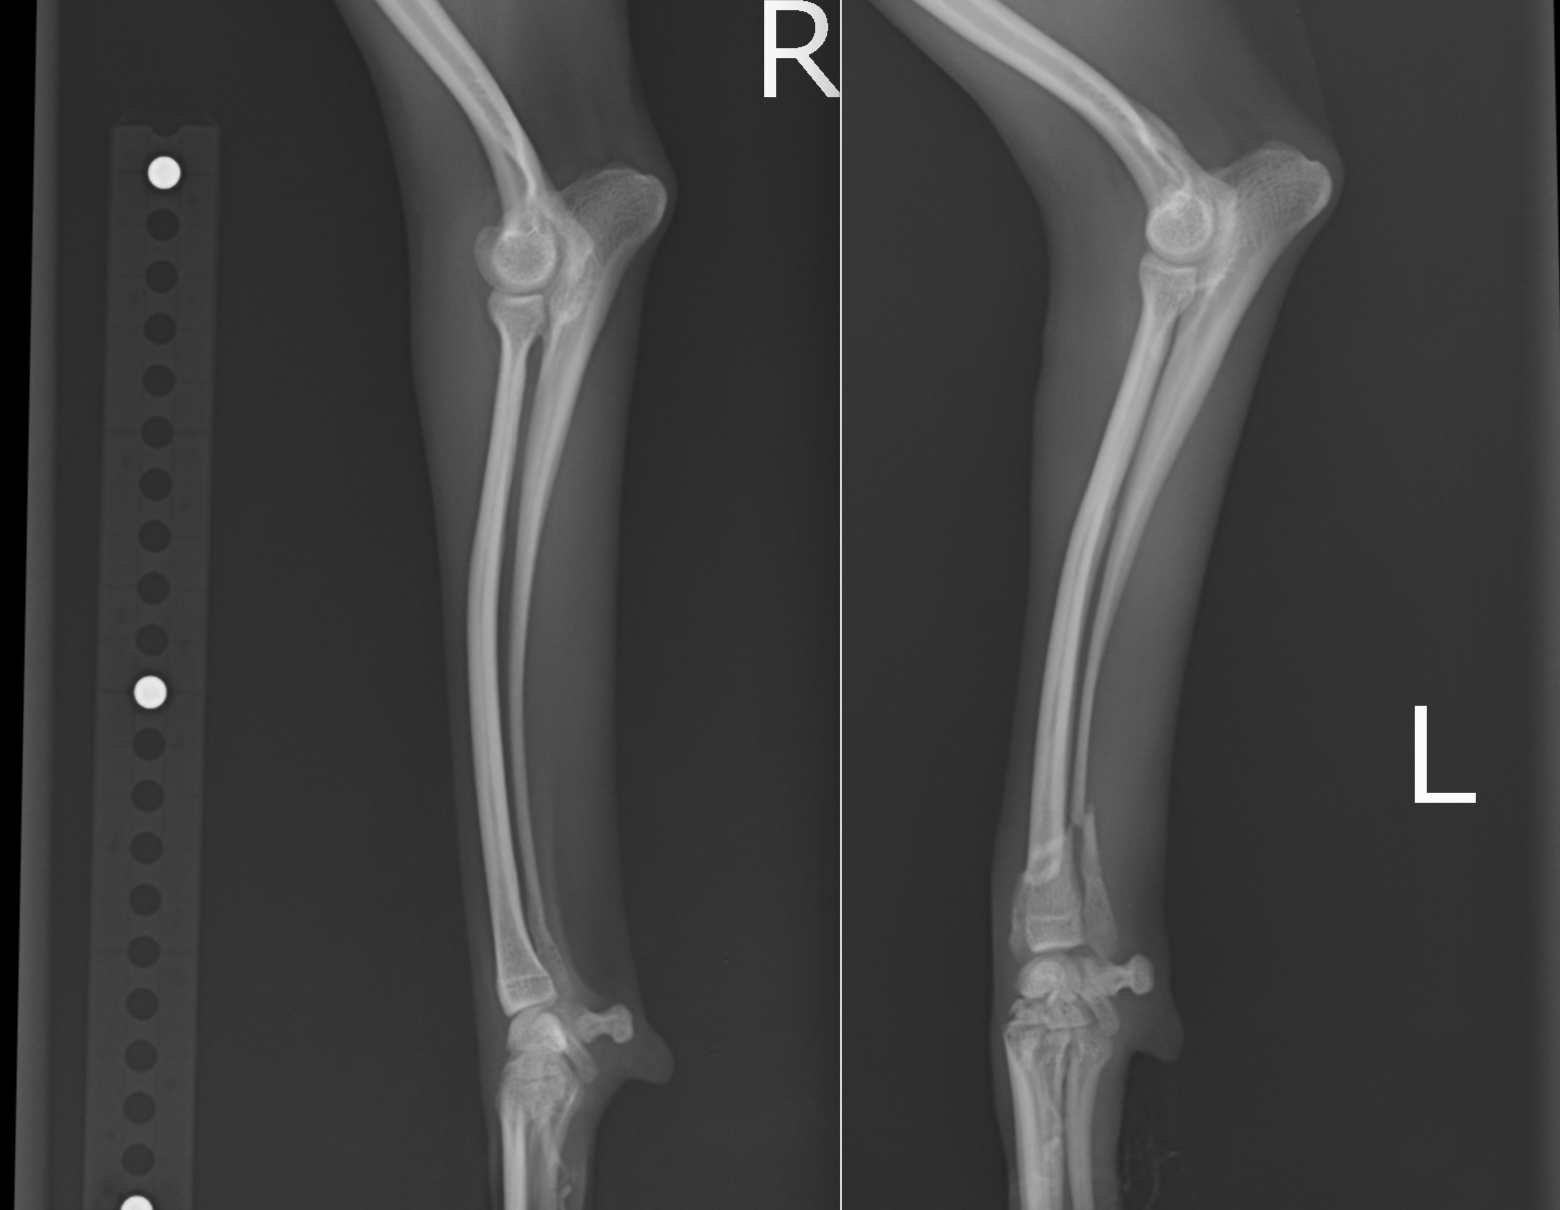

この子もプレートが破綻して2回めの手術をしているため、プレートが長くなっています。

術後経過は順調で2ヶ月ほどで正面のプレートを抜去しました。